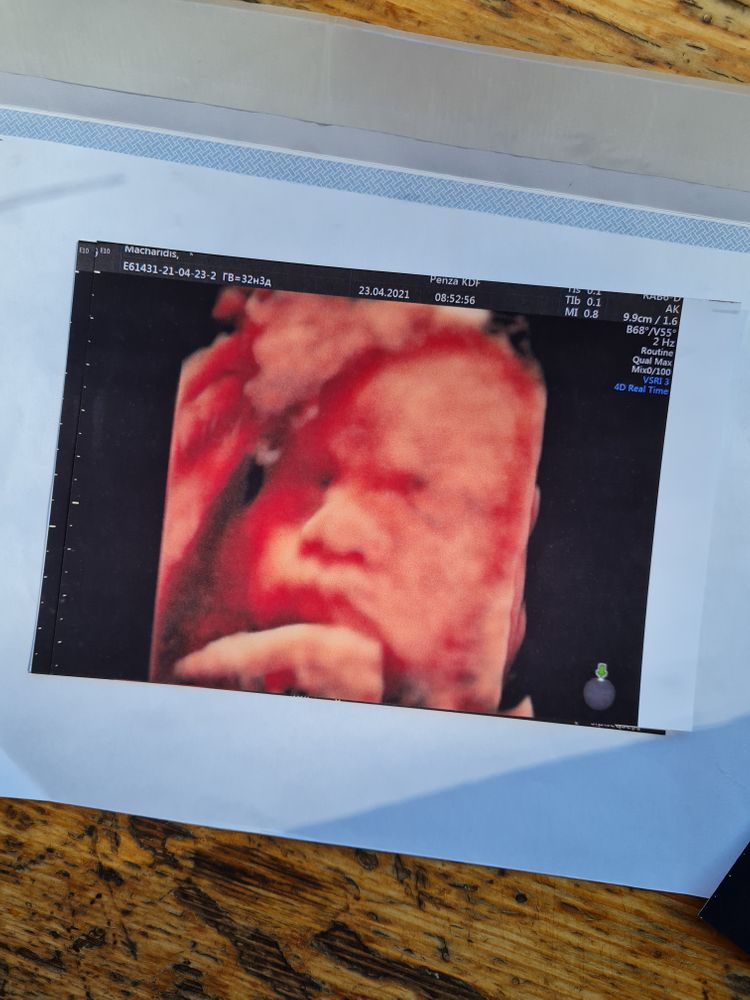

Ну и самое главное, мы посетили сегодня УЗИ) целых 6 недель я не была на узи, для меня это рекорд)

Человек наел щёчки, хотя я ожидала больше вес, верю, что это просто погрешность УЗИ) Вес 1950, все показатели в норме, стопа 6 см, волосы на затылке длинные, даже это посмотрели) Нарушений никаких нет и спасибо за это🙏

Копия сестрица)